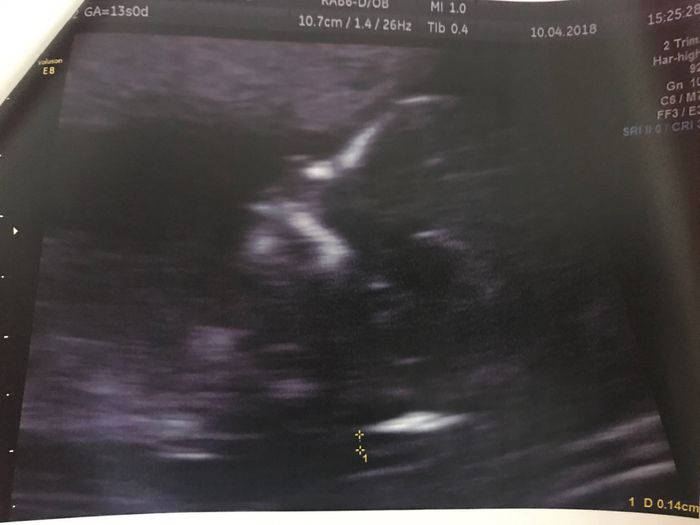

Ciao ragazze, scusate il mio ritardo di scrivervi, ieri ho fatto l'esame e l'ecografia a 13+0. La dottoressa dal l'ecografia ha detto che va tutto bene, la traslucenza e di 1,4. Il mio fagiolo era di 7,0 cm e si muoveva da matti..... Avrò la certezza...